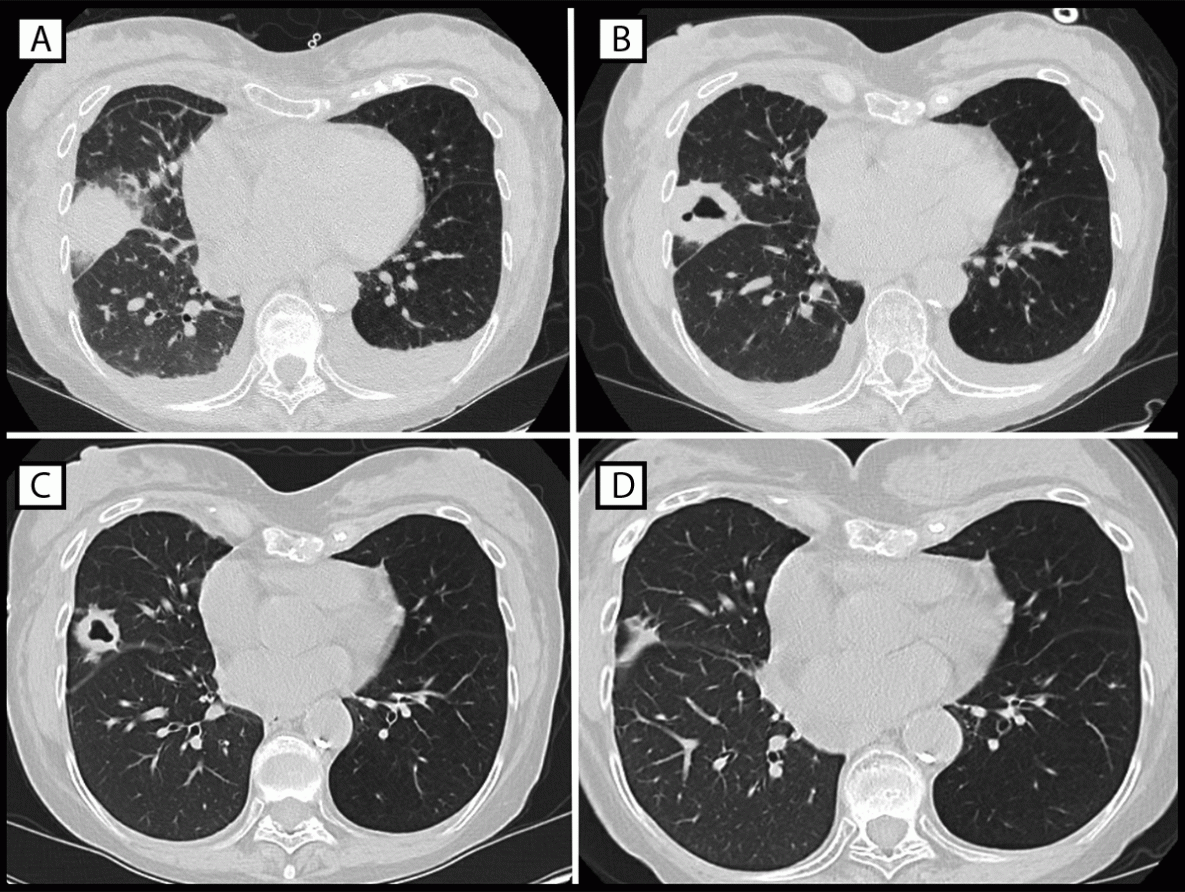

The first Legionnaires disease case was identified in a woman aged 70–79 years (patient A) who received a right lung transplant in May 2022. Nine days after transplantation, the patient’s laboratory results revealed an elevated white blood cell count and acute anemia, which prompted imaging studies. A computed tomography (CT) scan was performed based on these blood test results. The CT scan identified dense consolidation in the middle lobe of the donor lung, which evolved into a cavitary lesion during the subsequent week (Figure). A bronchoalveolar lavage specimen collected during early June tested positive for Legionella species other than Legionella pneumophila by nucleic acid amplification. Doxycycline treatment was initiated immediately after Legionella was identified in the lavage specimen, and the patient fully recovered. No further testing was performed to identify the species or rule out the presence of multiple Legionella species.

FIGURE. Computed tomography studies of the chest of patient A, who experienced infection with Legionella sp. (other than Legionella pneumophila) after receipt of a transplanted right lung from a donor who had drowned in fresh water, showing dense consolidative opacity with surrounding ground glass opacification (postoperative day 9) (A), thick-walled cavitation (postoperative day 16) (B), resolving lesion with thinning of cavity walls (postoperative day 29) (C), and continuing improvement (postoperative day 119) (D) — Philadelphia, Pennsylvania, May 2022